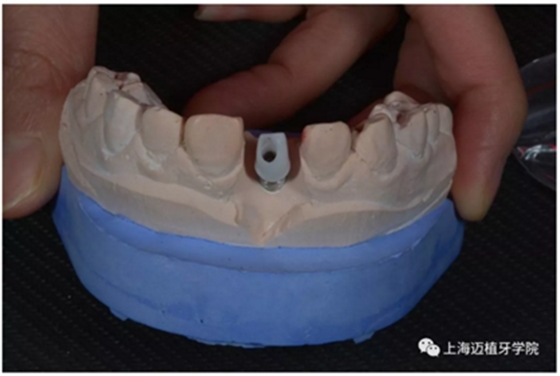

轉(zhuǎn)移模型

取工作模型

非工作模型